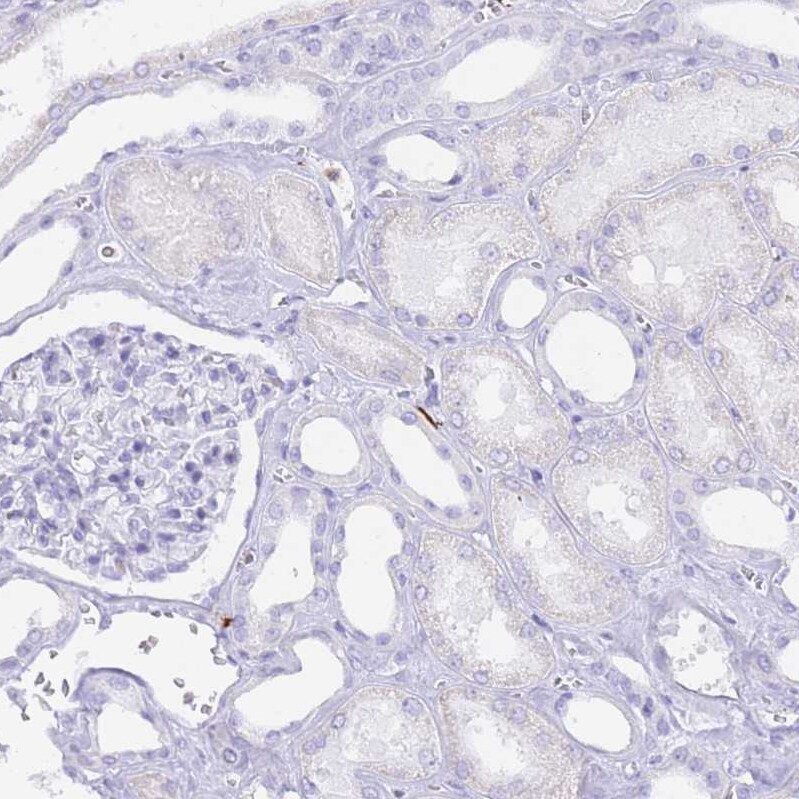

- Submitted by

- Invitrogen Antibodies (provider)

- Main image

- Experimental details

- Immunohistochemical analysis of HERC1 in human kidney using HERC1 Polyclonal Antibody (Product # PA5-62033) shows no cytoplasmic positivity in cells in tubules as expected.